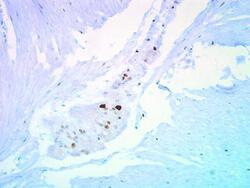

Supportive validation

- Submitted by

- Invitrogen Antibodies (provider)

- Main image

- Experimental details

- Immunohistochemical staining of human ulcerative colitis tissue using anti-p27 Kip1 Polyclonal Antibody (Product # PA5-27188).